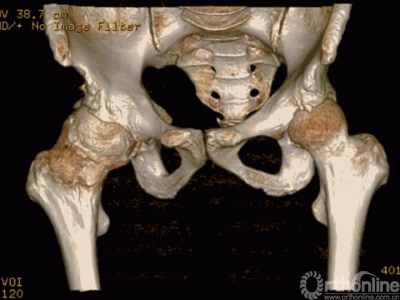

患者术前CT三维重建图像

由AI HIP系统对患者的髋关节CT数据进行人工智能分割与关键点识别,术者可根据智能分割与测量结果综合判断患者情况。如图可见,该患者关节内可见明显畸形。

对患者骨盆正位、特别是双侧髋关节局部特征进行观察,此例手术存在较多的骨性和软组织性陷阱。其一,患者为冠状面的双侧髋外翻畸形,双侧CCD角度高达148°,远远超出正常髋关节的生理范围。目前常规股骨假体最大的CCD角也仅有137°,个体化髋关节重建难度高。其二,右侧髋关节因骨性撞击导致股骨头粗大(左侧股骨头直径46mm,右侧股骨头直径54mm),由此导致髋关节周围关节囊360°膨胀性拉长,由此导致髋关节静态稳定结构松弛,术后脱位风险增加!其三,髋臼硬化、形变严重,术中髋臼解剖旋转中心处打磨容易出现偏差。其四,最棘手的是由于撞击导致外展肌过度延长,最终结果是右侧的髋臼偏心距和股骨偏心距均显著外移,由此带来髋关节动态稳定肌群的松弛和菲薄,术后脱位风险进一步增加!在如上困境中,选择常规假体进行手术,往往出现两个极端:要么下肢延长,要么关节脱位。常规术前计划系统,如等比例胶片法、或基于二维X线的计算机软件测量系统,均难以在两者间实现平衡。而基于人工智能深度学习技术与手术模拟算法、图像算法结合,依靠计算机辅助的方式来实现关节置换手术的三维术前规划--AI HIP系统,是解决上述问题的理想选择。